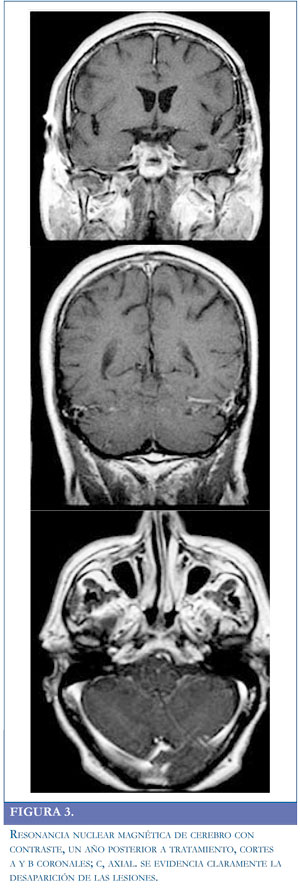

El paciente permaneció con cefalea pero mejora la hipertensión endocraneana. Los cultivos a la semana negativos y el paciente se estabilizó clínicamente. A los 25 días de su ingreso la resonancia de control no demostró clara mejoría y se realizó biopsia abierta de lesión temporal. A los 35 días de su ingreso el cultivo es positivo para Nocardia spp (Figura 2), por lo que se continúa manejo específico con TMP/SMX endovenoso hasta completar seis semanas. El manejo antifúngico y con esteroides se suspendió a los 15 días de su inicio al no tener clara mejoría y por los resultados icrobiológicos negativos. El paciente continuó la rehabilitación y a los dos meses se halla con leve alteración para la marcha sin diplopía ni síndrome parietal. Se continuó manejo oral con TMP/SMX hasta un año posterior a su hospitalización. En la resonancia magnética control tomada 18 meses posteriores a su ingreso, se evidenciaron cambios residuales no activos (Figura3). Se consideró resolución del cuadro y el paciente retornó a sus actividades.